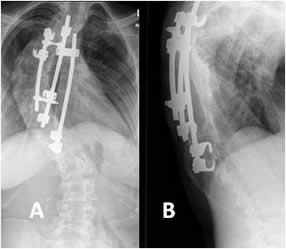

Fig 42 A. Corrección quirúrgica.

A: Rx lateral y B: Rx AP. Corrección de escoliosis dorsolumbar izquierda, mediante placas laterales.

Fig 42 B. Corrección quirúrgica.

A: Rx AP y B: Rx lateral. Fijación de escoliosis dorsal derecha, por medio de barras.